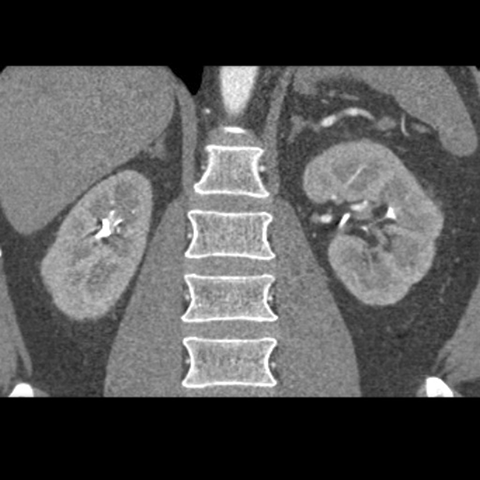

Adrenal glands (coronal, CT)